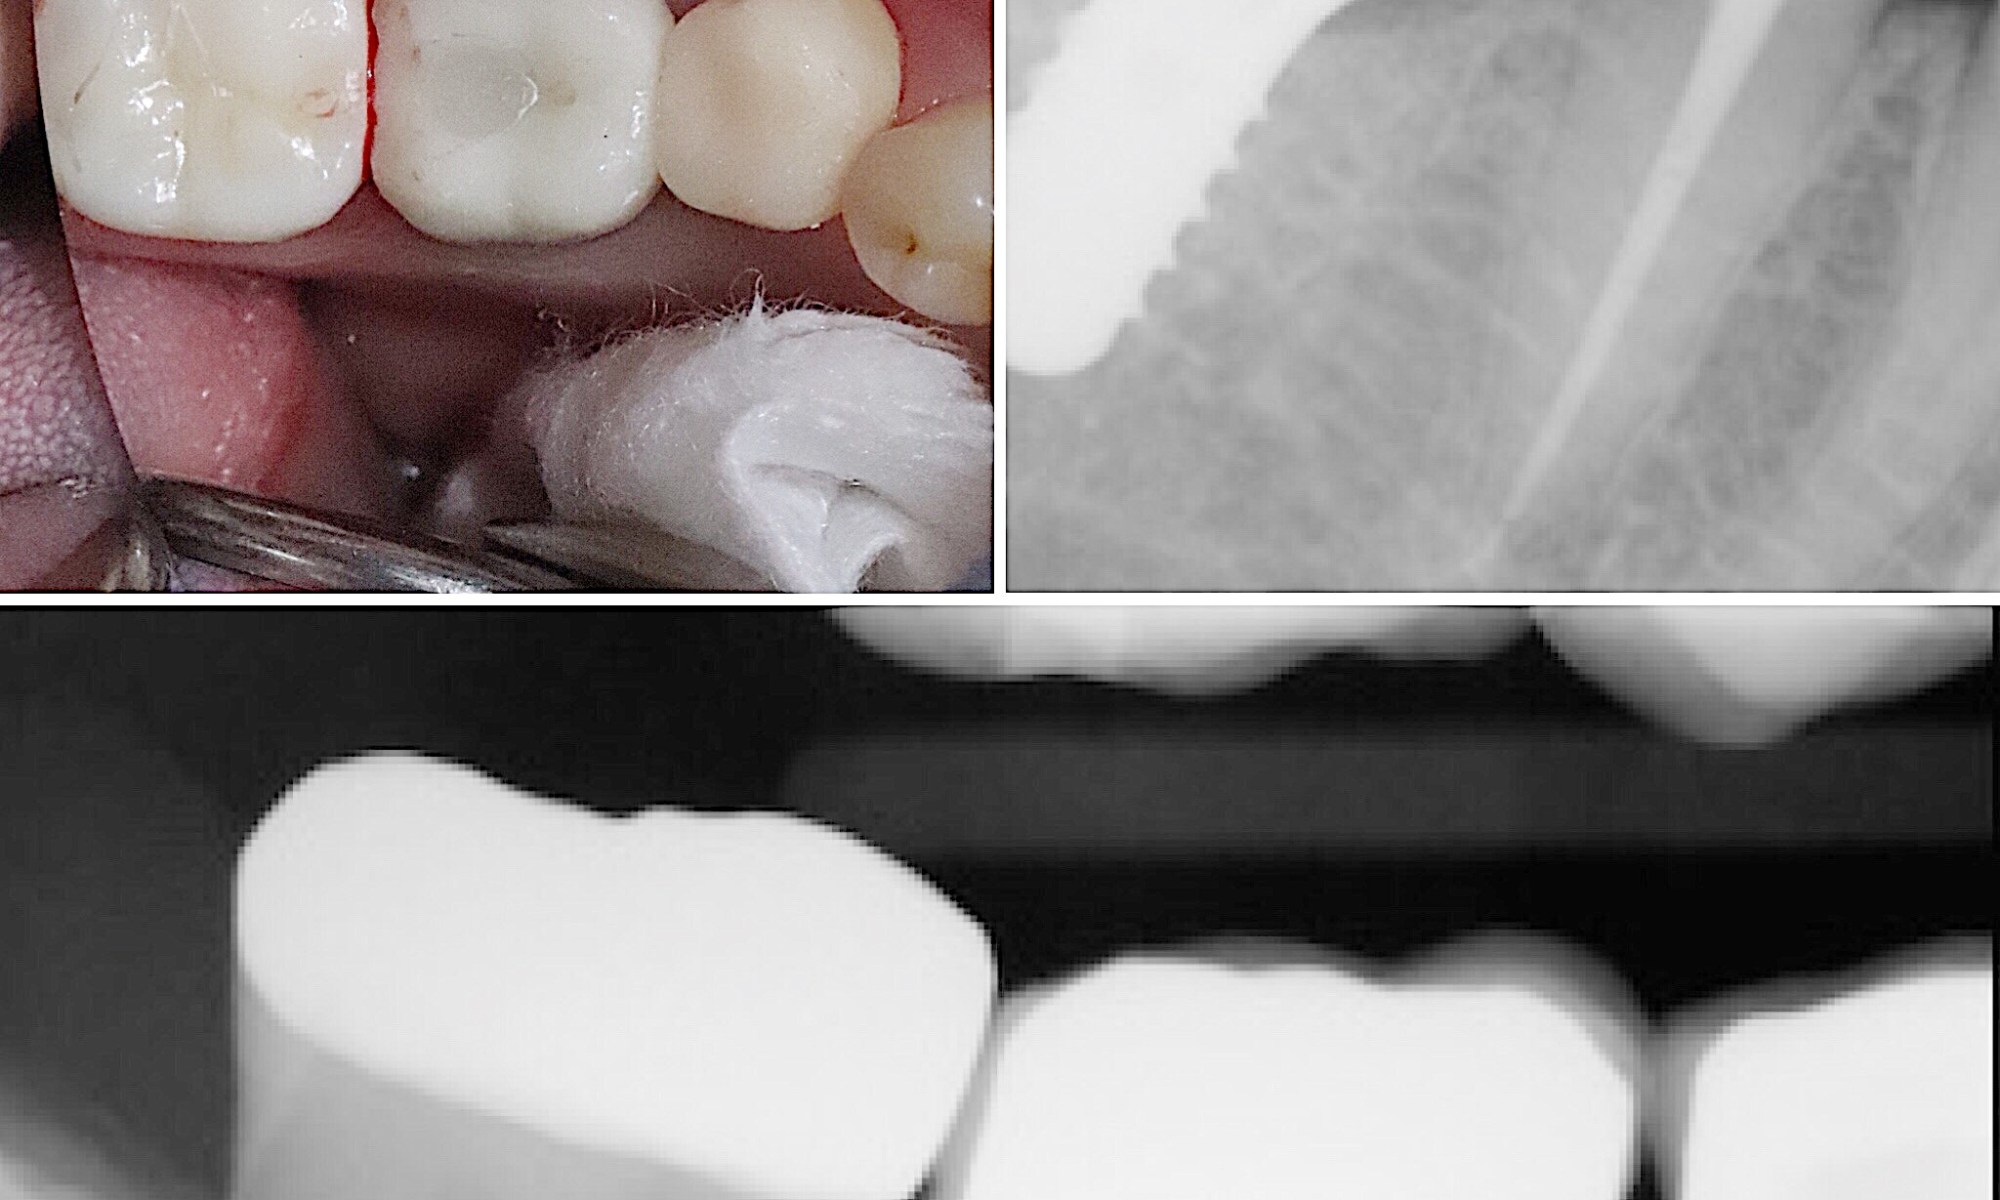

Very anxious patient came to see me with extensive dental needs. Here is an example of quadrant dentistry with multiple disciplines. Implant, root canal, crowns, and sedation were all involvement to keep the patient comfortable and healthy. Quality care is crucial, however, patient experience and comfort comes first. This patient is like family.